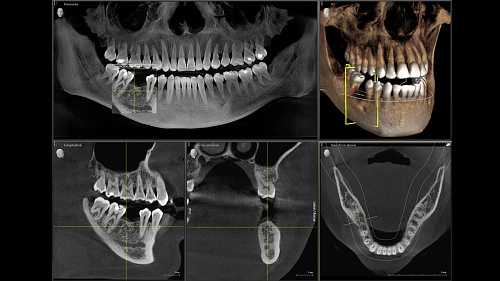

Диагностика последнего поколения, идеально решающая задачи рентгеновского обследования независимо от размеров клиники. Поля изображения зависят от определенной клинической картины, поэтому специалистам так удобно работать с ORTHOPHOS SL 3D. Данная установка делает объёмные картинки для одиночной реставрации в 3D качестве полностью всей челюсти такого размера, которого требуется.

Датчик DCS служит для выставления резкости снимков, причём его технологические особенности можно считать революционными для современного рынка стоматологического оборудования.

Планирование одиночной реставрации, эндодонтические исследования и пр. – для этого специалист может выбрать объёмные варианты 8 х 8 см или 11 х 10 см, также предлагается объём 5 х 5,5 см. Снимки в HD-качестве, стандартные настройки или выбор объёма обследования в зависимости от диагноза — всё это врач получает в отличном качестве, а для пациента излучение в районе исследования минимально.

Конструктивные особенности датчика DCS заключаются в превращении рентгеновского излучения в электрическую энергию. Обычная для таких случаев промежуточная стадия светового луча отсутствует. Другими словами, значительно снизив потери сигнала, производитель максимально улучшил чёткость.

С технологией SL можно за один сеанс получить огромное количество снимков. Те из них, где фокусировка наиболее чёткая, автоматически соединяются. В итоге одна процедура — снимки челюсти полностью в самом лучшем качестве. Даже нестандартные случаи не станут помехой в обследовании. К примеру, при ретинированных зубах уже после того, как снимок сделан, нужную область можно выделить подробнее, и в ещё одном рентгене необходимость отпадает.